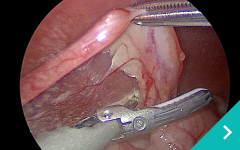

ミニマム創内視鏡下手術は腹腔鏡だけでは対処ができないような手術の際に、お腹にラッププロテクターという器具を設置して行う腹腔鏡と開腹手術を組み合わせた手術です。